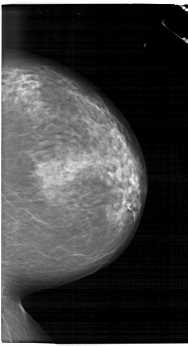

A_1657_1.LEFT_MLO

LEFT_MLO LINES 6721 PIXELS_PER_LINE 4246 BITS_PER_PIXEL 12 RESOLUTION 43.5 OVERLAY